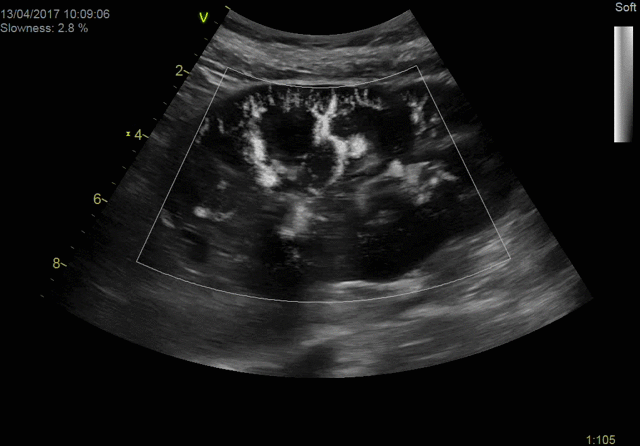

Экспертное качество изображений при проведении 2D TTE исследований и при обычной трансторакальной эхокардиографии дает возможность проводить сложные кардиологические исследования и получать достоверные результаты для назначения эффективного лечения.

Благодаря своим техническим возможностям система Vivid S70 позволяет получать достоверные данные для количественной оценки даже при проведении исследований пациентам с избыточным весом или пациентам состояние которых затрудняет проведение диагностики, а технология датчиков XDclear работающая в паре с платформой cSound гарантирует беспрецедентный уровень качества изображений.

- Органы брюшной полости

- Педиатрия

- Неонатология